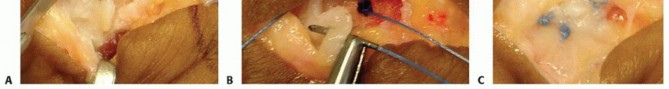

Open Surgical Repair of the Collateral Ligament

When dealing with a mid-substance tear, a purely ligamentous avulsion, or a confirmed Stener lesion, an open approach is mandatory to ensure anatomical restoration and appropriate tensioning.

-

Incision and Superficial Dissection:

For a UCL repair, a lazy-S or chevron-shaped incision is centered over the ulnar aspect of the MCP joint. The apex of the incision is typically placed dorsally to avoid placing a straight scar directly over the joint flexion crease, which can lead to restrictive contractures.

The skin flaps are elevated, taking great care to identify and protect the dorsal sensory branches of the ulnar nerve. These branches are mobilized and gently retracted dorsally using vessel loops. The underlying deep fascia is incised, exposing the transverse fibers of the adductor aponeurosis. -

Identifying the Pathology and the Stener Lesion:

At this stage, the surgeon must carefully inspect the anatomy. If a Stener lesion is present, the bulbous, torn proximal stump of the UCL will be clearly visible lying superficial to the adductor aponeurosis.

To access the joint and the native footprint, the adductor aponeurosis must be incised. We typically make a longitudinal incision through the aponeurosis, parallel to the extensor tendon, leaving a sufficient cuff of tissue volarly for later robust repair. The aponeurosis is reflected volarly, exposing the underlying joint capsule and the torn ends of the collateral ligament. -

Footprint Preparation and Anchor Placement:

The joint is inspected, and any intra-articular debris or osteochondral loose bodies are removed. The anatomic footprint of the ligament—most commonly on the volar-ulnar base of the proximal phalanx—is identified. This area is meticulously decorticated using a small curette or a motorized burr to expose bleeding cancellous bone, which is essential for biological healing of the ligament-to-bone interface.

A micro-suture anchor (typically 1.3 mm to 1.5 mm in diameter, loaded with high-strength non-absorbable suture) is inserted into the prepared footprint. The anchor must be placed at an angle of approximately 45 degrees to the articular surface to ensure adequate bone purchase and avoid iatrogenic penetration into the joint space.

Ligament Repair and Tensioning:

The sutures from the anchor are passed through the distal stump of the UCL using a locking configuration, such as a modified Krakow or Mason-Allen stitch, to ensure a secure, tear-resistant grasp of the tissue.

Crucially, the joint is held in approximately 15 to 20 degrees of flexion and slight ulnar deviation during knot tying. This position appropriately tensions the proper collateral ligament while ensuring the volar plate is not over-constrained. If the accessory collateral ligament or volar plate is also torn, these structures are incorporated into the repair or sutured separately to restore full multi-planar stability.